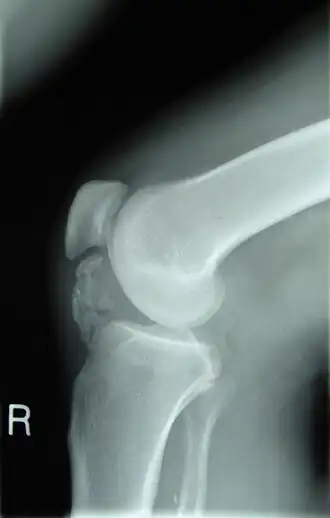

Рентгенограмма колена пациента, больного остеохондромой. Видно окостенение околосухожильных тканей

Остеохондро́ма (лат. osteochondroma, множ. osteochondromata, костнохрящевой экзостоз) — доброкачественная опухоль кости, образующаяся из хрящевых клеток. Она представляет собой бесцветную массу, которая чаще всего образуется в возрасте от 10 до 25 лет на эпифизе длинной трубчатой кости, может также встречаться и в плоских костях.